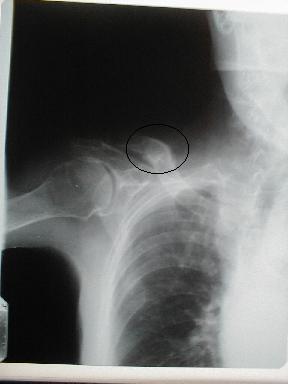

| 11月21日受傷後41日目 |